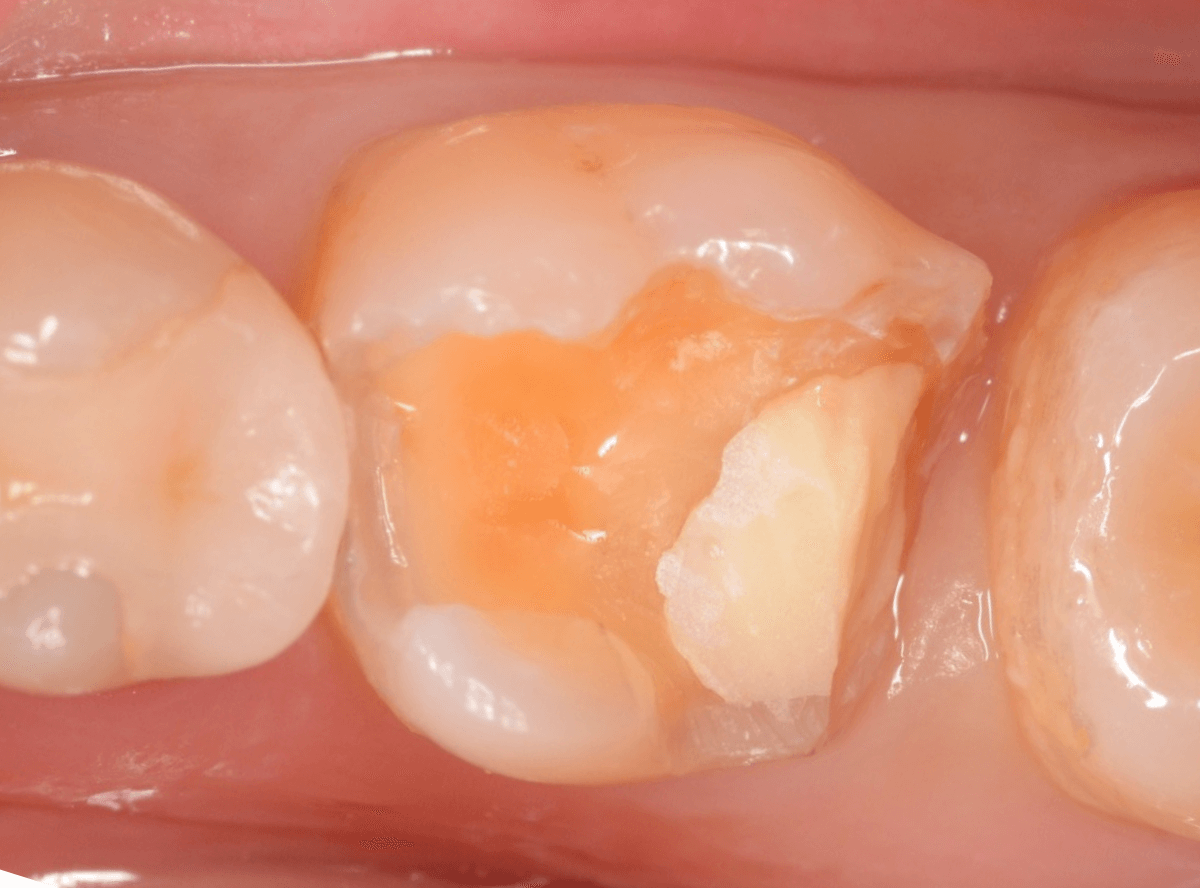

Case.30 上の奥歯のセラミック治療

メンテナンス中に、虫歯が見つかった方のケースです。

大きな虫歯でしたので、しばらく経過観察しましたが、特に症状もありませんでしたので、患者さんの希望に伴い、ジルコニア・インレーで治療をします。

セラミックが精密にsetできるように、歯をトリミングします。

治療後の状態です。

ジルコニア・インレーはE-MAX・インレーより審美性に劣るのですが、患者さんにもご満足いただける仕上がりになり、ホッとしました。